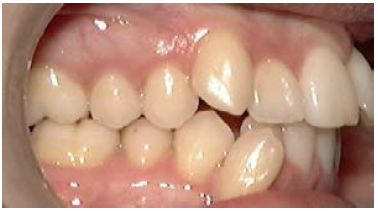

The maxillary first molar is forward of the normal molar relationship in Class II. The mesiobuccal cusp of the maxillary first molar is mesial to the buccal groove of the mandibular first molar. In Class II Division 1 (Figure 2), the maxillary incisors are in labio-version, or protruding. In Class II Division 2 (Figure 3), the maxillary central incisors are in linguo-version (retruded) and lateral incisors are protruded. In Class III the maxillary first molar is distal of the normal molar relationship. The mesiobuccal cusp of the maxillary first molar is distal to the buccal groove of the mandibular first molar.

Figure 2. Class II Division 1.

Figure 2